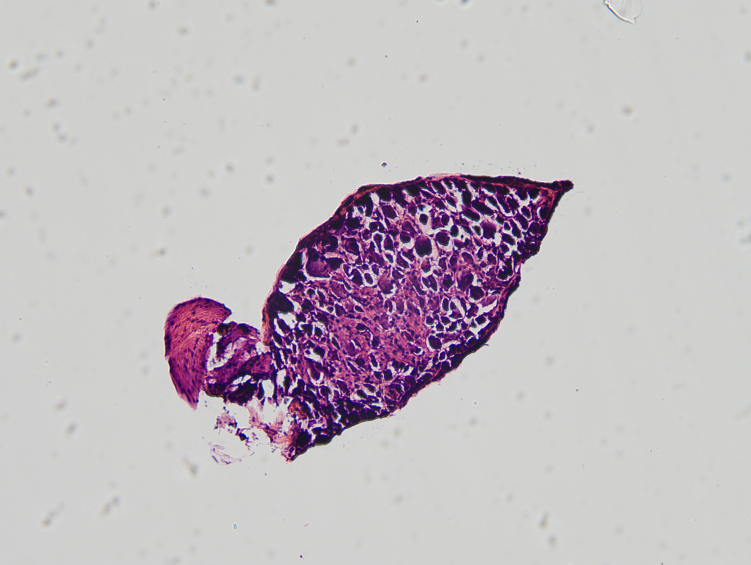

6. 坐骨神经和L4-6背根神经节;

7. 背根神经节HE染色。